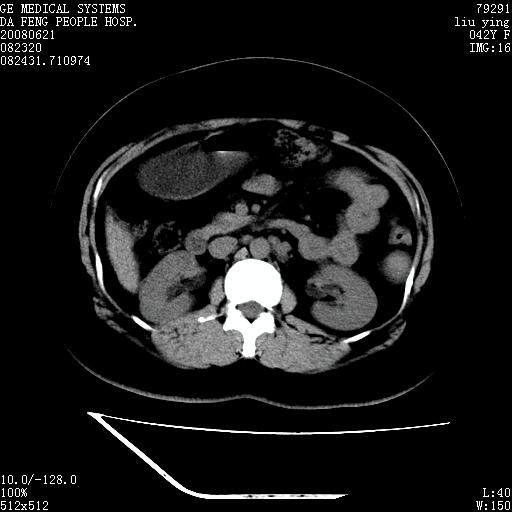

标题: CT14225:女性46岁。当地B超示肝内占位,来我院作CT检查。请 [打印本页]

标题: CT14225:女性46岁。当地B超示肝内占位,来我院作CT检查。请

速升速降,支持肝癌.脾体积增大,形态欠规整,请询问病史是否做过脾动脉栓塞.

速升速降,支持肝癌可能。

右叶肝癌灶;慢性胆囊炎,不除外占位;;副脾可能性

快进快出,符合肝癌表现-----------

肝内结节强化特点符合原发性肝癌表现,脾脏改变考虑为增大及先天发育所致。

动脉期病原灶明显强化高于肝密度且中央有无强化区,静脉期强化程度下降明显,延迟低于肝密度,考虑肝腺瘤可能性大,

肝内结节强化特点:快进快出符合原发性肝癌表现

此患者虽然符合快进的特点,却不符合快出的特点,因为门脉期几乎是等密度,不符合肝癌的增强表现,所以我考虑肝局灶性结节增生可能性大